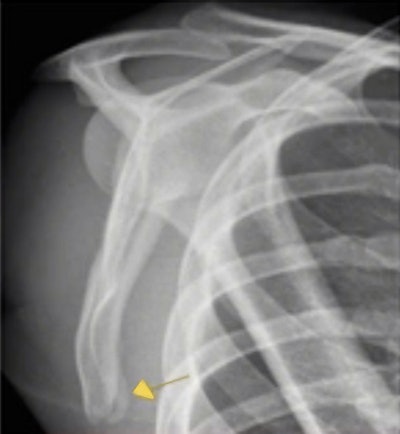

X-ray showed a minimally displaced fracture in the scapula of this professional football player. The diagnosis was later confirmed by CT.The MRI showed no acute bone injury, bone contusion, or fracture; no ligamentous injury; and no soft tissue edema or swelling. However, the MRI scan did not depict the shoulder completely, and the radiologist recommended further scapula MRI or CT to rule out fracture. On day three, the player felt better and was back in full training but he was still stiffer in the shoulder than expected, so Ahmed arranged an x-ray. The x-ray report received at 4 p.m. showed a minimally displaced fracture of the inferior border of the right scapula.

Ahmed discussed the case with the head physio, radiologist Dr. Gajan Rajeswaran of the Fortius Clinic, and also with the orthopedic surgeon, the player, the manager, and the football director. Within half an hour, it was decided that a CT was necessary, and this was performed at 6:30 p.m. The report was ready by 7:53 p.m., which confirmed the presence of a fracture.